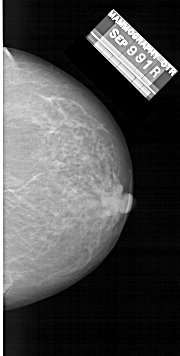

A_1481_1.RIGHT_MLO

RIGHT_CC LINES 6046 PIXELS_PER_LINE 3046 BITS_PER_PIXEL 12 RESOLUTION 43.5 NON_OVERLAY